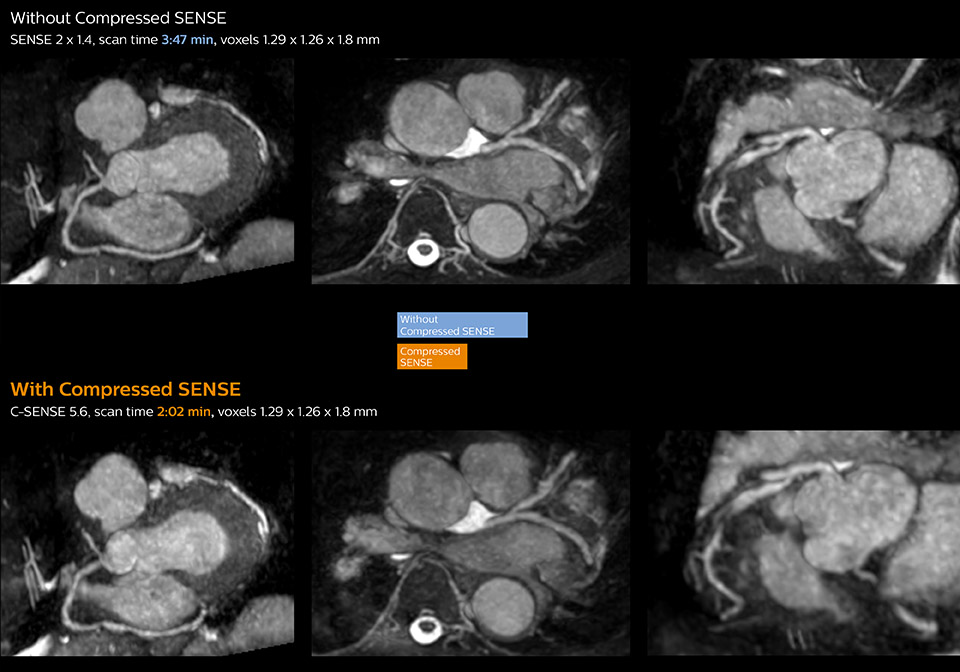

3D whole heart MRI and coronary arteries w/wo Compressed SENSE

These images with and without Compressed SENSE were acquired on Ingenia 1.5T.

“Typically, in scans with high contrast, such as 2D balanced TFE cine, a quite high C-SENSE factor may be used. When we tried a higher C-SENSE factor, we saw still no significant influence on cardiac ejection fraction, but 2D image quality started to decline. For coronary imaging, we use a C-SENSE factor of 3 in 3D balanced TFE, or even up to 4 when contrast is high.”